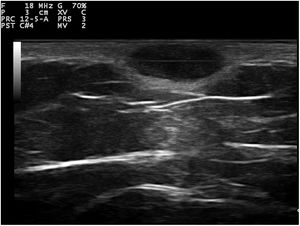

La dermatoscopía reveló un fondo azul violáceo homogéneo, sin estructuras vasculares en su interior, rodeado por un retículo pigmentado fino monomorfo (fig. 1B). En el estudio ecográfico se observó un tumor subcutáneo, constituido por áreas hipoecogénicas (fig. 2) y que no presentaba flujo en modo Doppler color. Se extirpó la lesión con los posibles diagnósticos de sospecha de dermatofibroma aneurismático, hemangioma microvenular, nevus combinado y melanoma. En el estudio histológico se observó un nódulo dérmico constituido por una proliferación de células histiocíticas con la presencia de múltiples capilares y hemosiderófagos, así como de bandas de colágeno en la periferia (fig. 3A). Además, destacaban ectasias y canales sin revestimiento endotelial con hematíes extravasados y hemosiderina (fig. 3B). La inmunohistoquímica fue positiva para CD 68 (fig. 3C) y factor XIII, y negativa para CD 31, CD 34 (fig. 3D) y S100.

Ecográficamente los dermatofibromas suelen verse como áreas hipoecoicas y mal definidas que distorsionan y amplían los folículos pilosos y que no contienen depósitos cálcicos. En el doppler color suelen ser hipovasculares, aunque pueden mostrar vasos arteriales y venosos delgados de flujo lento. En la ecografía del DFA se han descrito zonas anecoicas sin flujo en el Doppler, que se corresponderían histológicamente con áreas de hemorragia. Además, se pueden encontrar áreas con flujo que estarían en relación con zonas vasculares y celulares del tumor3–5.